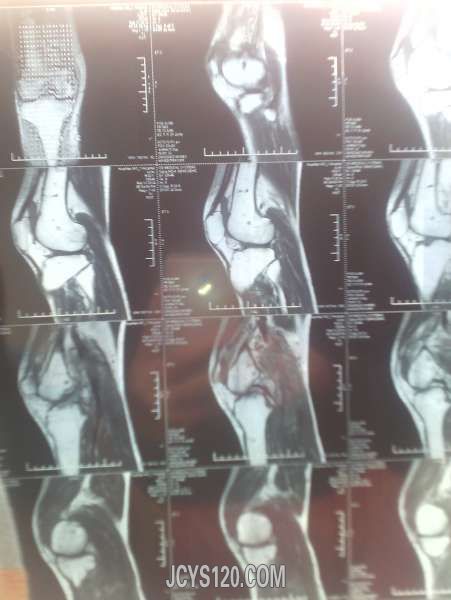

患者33岁男 因路滑扭伤!随即到医院检查,一般情况尚可,右侧膝关节。小腿腹部肿胀疼痛,磁共振影像如下,手机拍摄不是那么清楚!愿个为同行给点建议!需要做关节腔镜手术吗?有没有什么处理的方法给说说!!!

这种核磁影像不是熟悉,希望影像版版主给看看,或者楼主干脆把报告单一并发上来!

谷维素 发表于 2014-2-12 18:44 static/image/common/back.gif 这种核磁影像不是熟悉,希望影像版版主给看看,或者楼主干脆把报告单一并发上来! 谢谢回复!我也是看不太明白!毕竟见的太少~忘高手赐教!!!!

膝关节外力引起的损伤,较轻是以皮肤肌肉肌腱的损伤,严重时则出现半月板撕裂伤,髌骨的骨折。对于皮肤肌肉肌腱的损伤给予常规治疗即可,当出现半月板撕裂伤时可采取半月板的修补或切除术,这些度需要在关节镜下完成,髌骨骨折一般采用功能位的石膏固定。

体检下前后交叉韧带,侧副韧带有没有损伤,膝关节正侧位X片就够了,小腿后腹部肿明显一般是腓肠肌损伤,检查下跟腱有没有损伤,如果有问题再分别撕裂伤还是断裂伤,按情况相应处理,单肿胀用消炎止痛软胶外敷3-5天就可以了。大医院很多检查浪费。。。

片子看不懂,如果没有其他,肿胀是外伤导致静脉回流不畅所致,静滴几天丹参和七叶皂苷钠好的快些。

片子看不懂,患者没有住院。我们可以小心的给与云南白药,龙血竭胶囊治疗,但要注意观察。